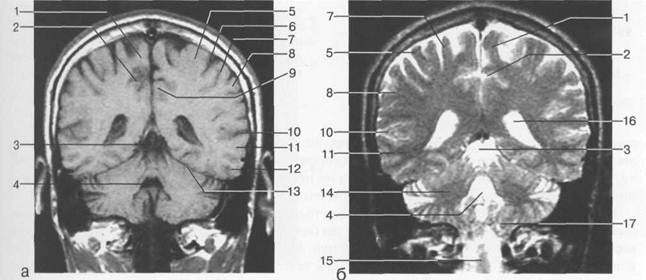

Рис. 1.15. Уровень лобных рогов боковых желудочков. Коронарные МРТ-срезы: а — Т1-взвешенное изображение; б — Т2-взвешенное изображение.

1 — межполушарная щель; 2 — поясная борозда; 3 — лобный рог; 4 — прозрачная перегородка; 5 — кора островка; 6 — верхняя лобная извилина; 7 — средняя лобная извилина; 8 — центральная борозда; 9 — мозолистое тело; 10 — хвостатое ядро; 11 — латеральная щель; 12 — внутренняя сонная артерия; 13 — внутренняя капсула; 14 — хиазма.